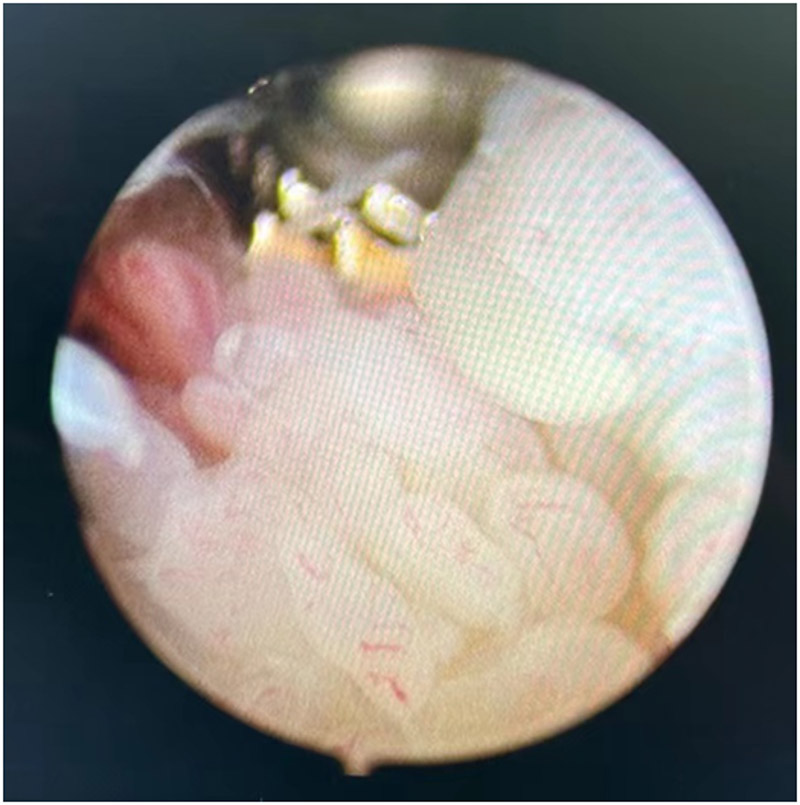

做好充分的術前準備后,醫生使用關節鏡微創技術,通過2個0.5厘米大小的切口為丁伯進行了關節鏡下的滑膜清理手術治療。術中發現腕關節內大量的炎性增生滑膜,部分滑膜已經開始侵蝕關節軟骨。這些像水草一樣的增生滑膜正是丁伯腕關節反復腫脹疼痛的罪魁禍首。